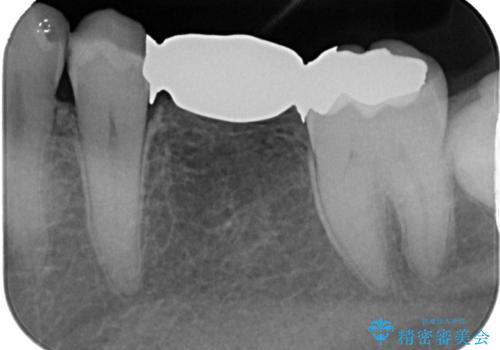

- 外れやすい銀歯をやり替えたいと来院された患者様です。

他院にて治療したインレーブリッジが何回か外れてつけ直しを繰り返しているため、外れないようにしてほしいとのことでした。

できるだけ外科処置は避けたいという患者様の希望と、すでにブリッジの土台となる両隣の歯を削って治療していることを考慮し、患者様と相談の上、今回はインプラントではなくフルジルコニアブリッジで治療することとしました。

より外れにくく精度の高いブリッジにするため、事前に親知らずの抜歯を当院で行いました。